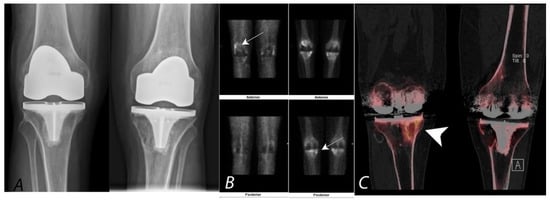

6. Hip Pain

7. Knee Pain